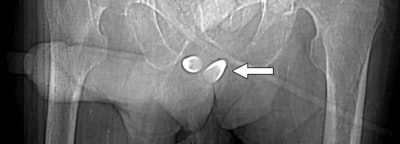

In addition, silicone injections can show up on imaging exams, as well as facial augmentations achieved via neurotoxin injections or fillers, such as calcium hydroxylapatite or hyaluronic acid.